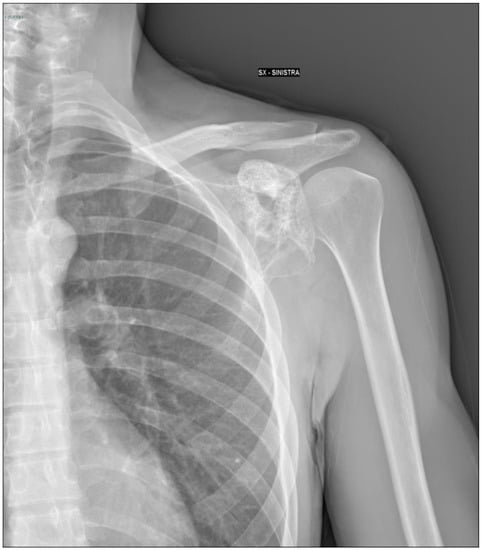

2.1. Oncological Staging

2.2. Prostheses Project